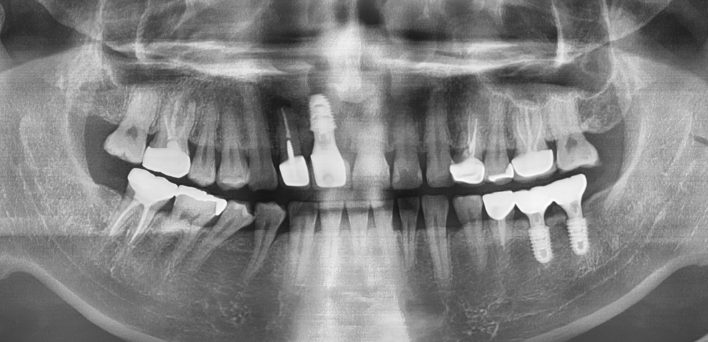

임플란트 케이스

임플란트 Before & After

The seoul dental clinic

※ 더서울치과의원은 의료법을 준수하며 위 케이스는 실제 환자의 동의를 얻은 사례로 치료 전, 후가 동일한 환경에서 촬영되었습니다.

환자 케이스에 따라 부작용이 발생할 수 있습니다. 이 부분은 의료진의 충분한 상담과 체크를 통해 예방하고 줄일 수 있습니다.

[임플란트 부작용] 수술 후 관리가 소홀할 경우 출혈, 주위염 등의 부작용이 발생할 수 있어 구강 위생을 철저히 유지하고, 정기적인 검진을 통해 상태를 점검하는 것이 중요합니다.